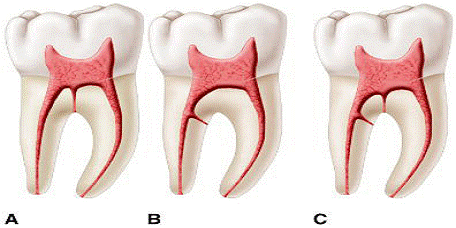

Inca de la inceputurile endodontiei Hess si Zurcher* pana la cele mai recente studii au demonstrate complexitatile anatomiei sistemului endodontic(figura 7). A fost stabilit ca un canal cu un singur foramen este mai de graba exceptia si nu regula. Studiile au aratat multiplele foramina, canale aditionale, delte, istmuri, bucle, canale in forma de C si canale laterale la cei mai multi dinti.* De asemenea in timpul tratamentului fiecarui dinte, medicul trebuie sa-si asume complexitatile anatomice ce pot aparea si care pot fi considerate normale.

Medicul trebuie sa fie familiar cu variatele cai pe care canalele le pot lua pana la apex. Sistemul este complex, canalele putand sa se ramifice, divide si apoi uni. Weine a clasificat sistemul endodontic in patru clase de baza ce se pot regasii in orice radacina(figura 8).

Vertuci, folosind dintii transparentizati la care sistemul endodontic a fost colorat cu hematoxilina, a descoperit un sistem mult mai complex(figura 9). Ei au identificat opt tipuri de sisteme ce pot fi descries dupa cum urmeaza.

Figura 9. Clasificarea lui

Vertucci

Singurul dinte ce a prezentat toate tipurile de sisteme a fost premolarul 2 superior.